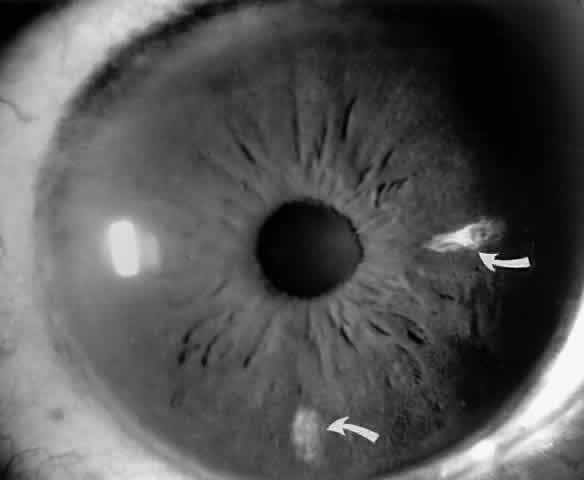

Iris Atrophy and Neovascularization

Occlusions of the iris vessels can result in atrophy, and patients may present with asymptomatic white patches of the iris.50,51 The area of atrophy may be extensive (Fig. 2) and may be associated with pupillary irregularity. Iris neovascularization may develop in eyes with chronic retinal detachment or major arteriole occlusions and can in rare cases cause a secondary neovascular glaucoma.52

Fig. 2. Iris infarcts in a patient with SC disease (arrows).